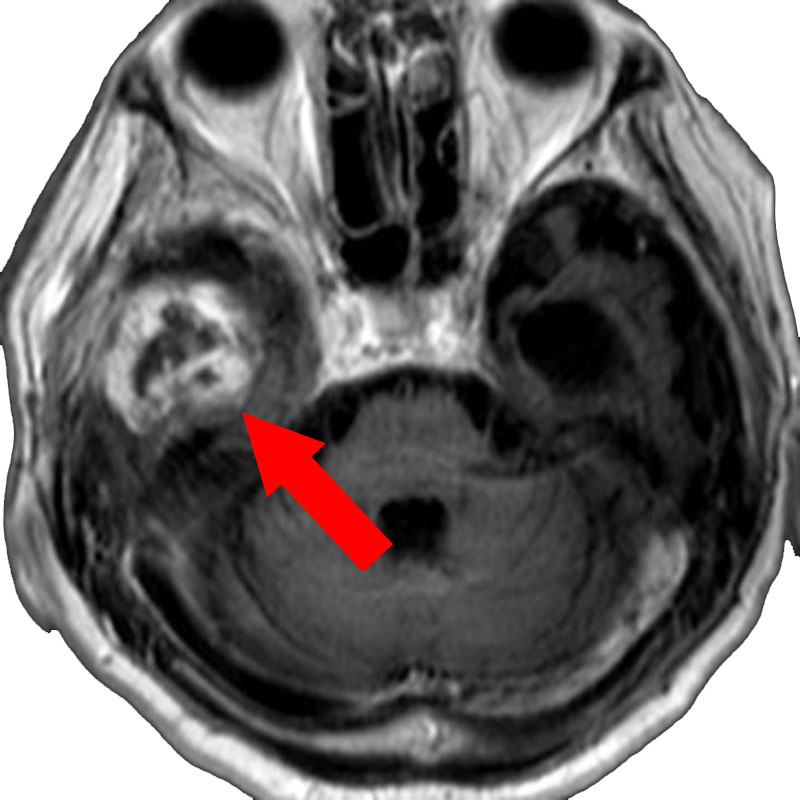

517

'24年3月

10代

小脳血管芽腫

頭蓋内腫瘍摘出術

No.’24_19 手術前1

No.’24_19 手術前2